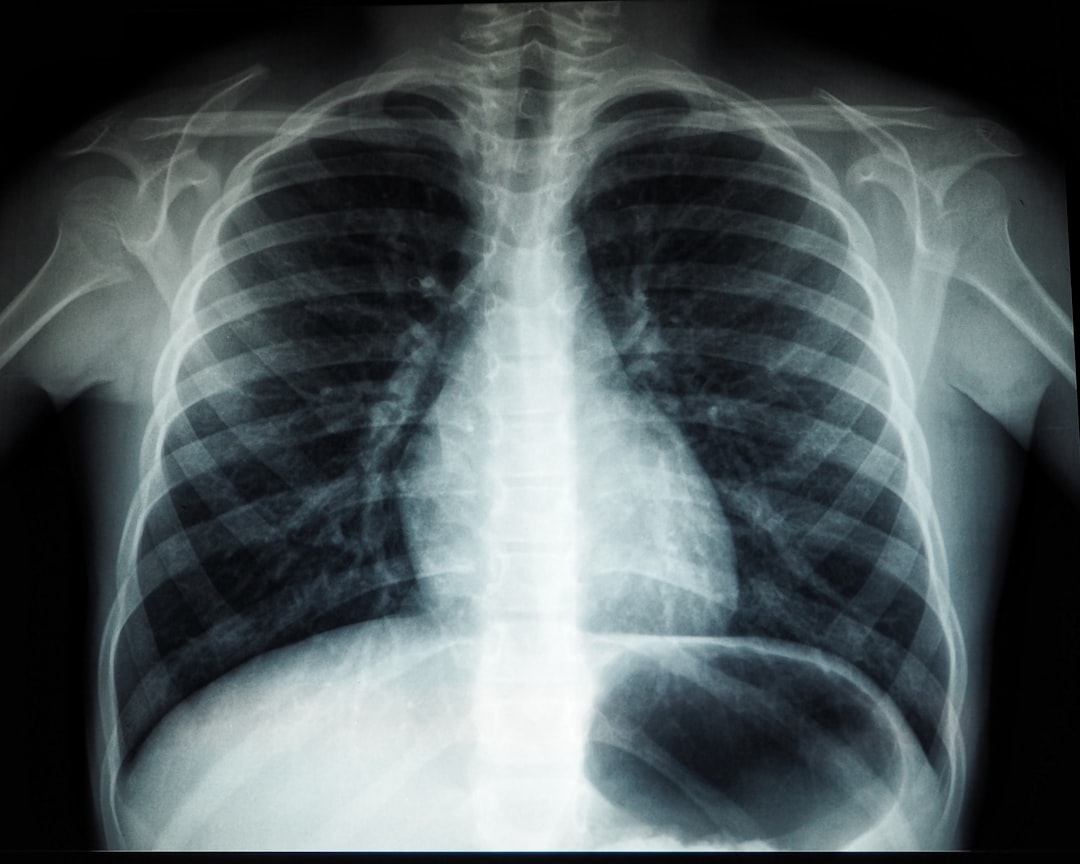

결핵검사는 간단하게 혈액 검사나 흉부 X선 촬영 등을 통해 진행됩니다. 검사 비용이 부담스럽거나 심리적 저항이 있는 분들도 보건소를 이용하면 비용 걱정 없이 검사를 받을 수 있어요. 아, 여러분은 최근에 약속을 잊고 있었던 검진 예약이 있으시죠? 지금이라도 다시 검토해 보세요!

두 번째 단계는 검사입니다. 흉부 X선 촬영과 가래 검사 등의 방법으로 진행됩니다. 이 과정에서 주의해야 할 점은 저마다의 특성이 있기 때문에, 증상에 따라 적절한 검사가 실시된다는 점입니다. 검사 후에는 대기하는 시간이 조금 필요하다는 점을 염두에 두세요.